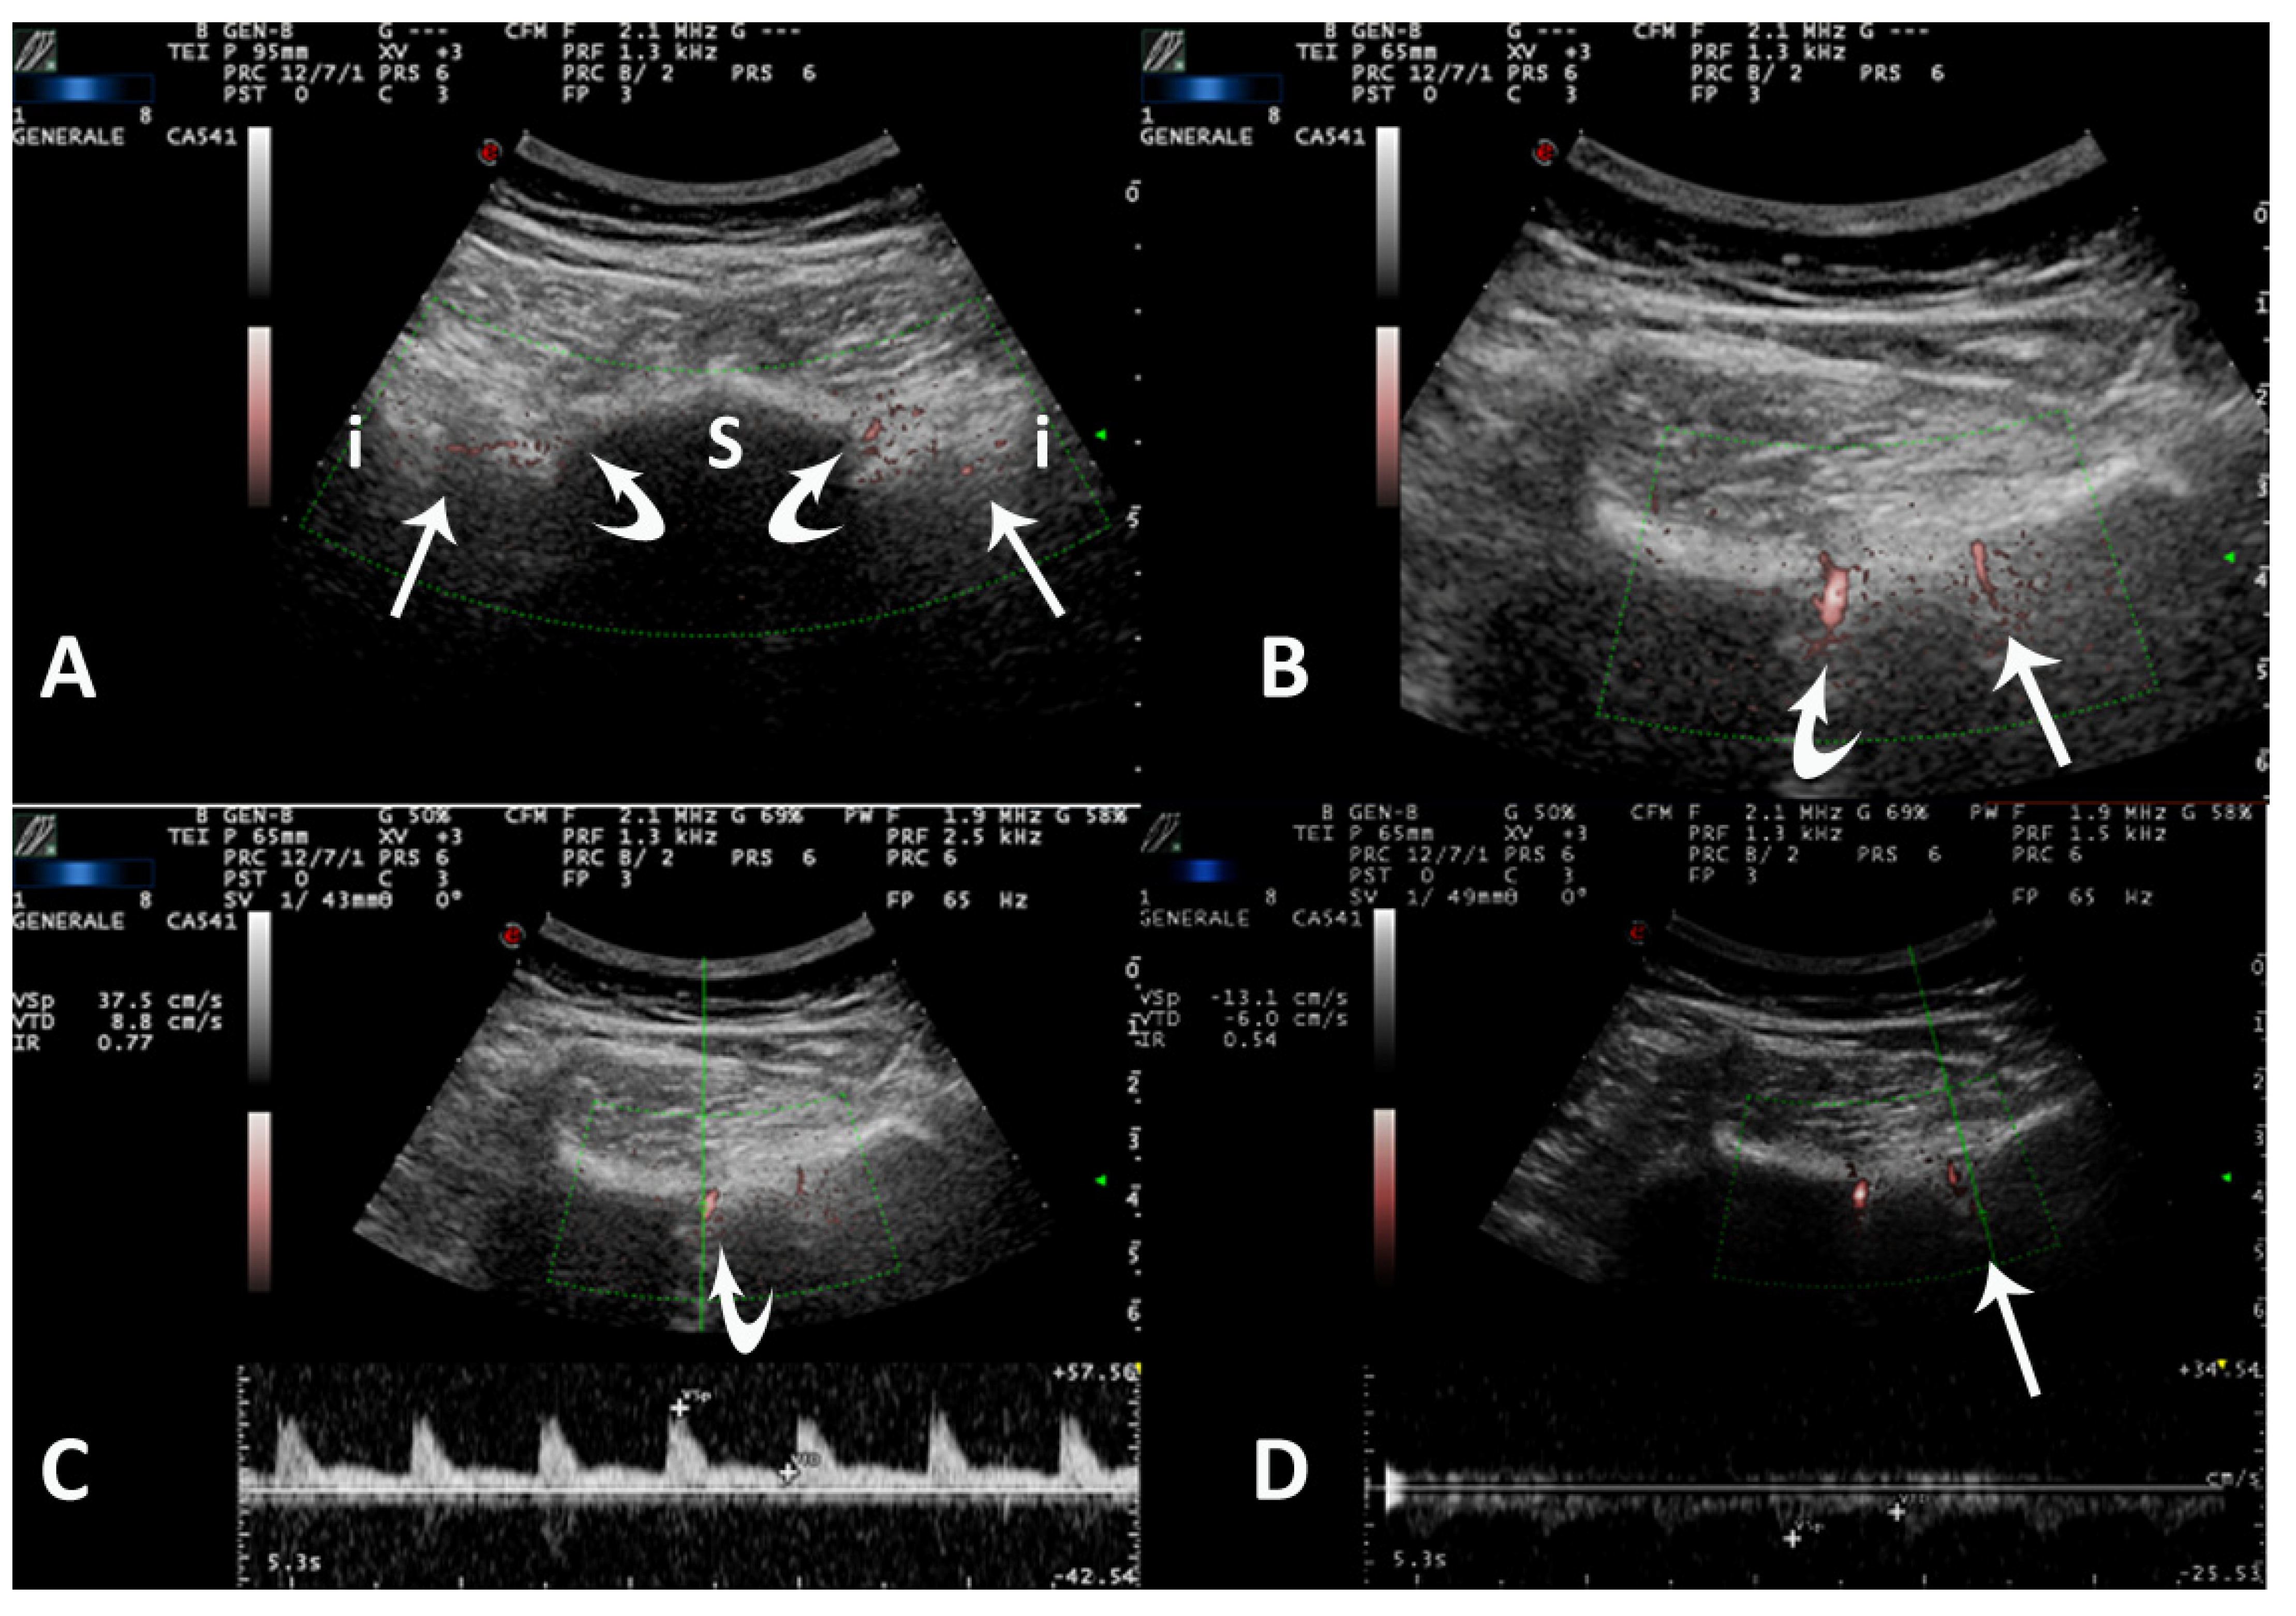

- Falsetti, P.; Conticini, E.; Mazzei, M.A.; Baldi, C.; Sota, J.; Bardelli, M.; Gentileschi, S.; D’Alessandro, R.; Al Khayyat, S.G.; Acciai, C.; et al. Power and spectral Doppler ultrasound in suspected active sacroiliitis: A comparison with magnetic resonance imaging as gold standard. Rheumatology 2021, 60, 1338–1345. [Google Scholar] [CrossRef]